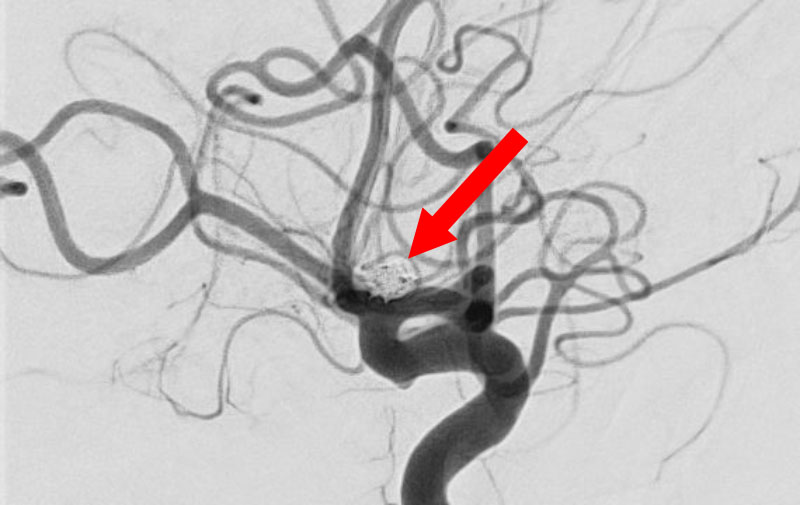

脳動静脈奇形

20代

愛知県の病院

No.1570 手術前

No.1570 手術中

No.1570 手術後